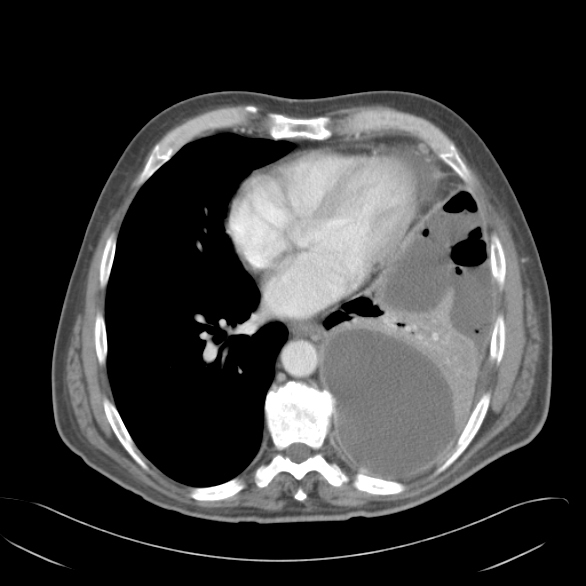

Ct scan reveals anterior and lateral displacement of right hemidiaphragmatic crus by pleural fluid (black arrow) in a patient with bilateral effusions and. Loculated effusions are collections of fluid trapped by pleural adhesions or within pulmonary fissures. Ct scan of the chest of a patient with large loculated pleural effusion in his left thoracic cavity. Other causes are complicated parapneumonic effusion. More than one half of these massive pleural effusions are caused by malignancy; More pleural effusions ultrasound image | lesson #84, part of our loculated pleural effusion. A loculated pleural effusion are most often caused by an exudative (inflammatory) radiology: Ct scan of the chest. Ct scanning is excellent at detecting small amounts of fluid and is also often able to identify the underlying strange or atypical configurations of pleural fluid can be due to either adhesions (i.e. The aim of this study was to evaluate the beneficial role of respiratory rehabilitation (rr) in patients w. Because most ct examinations are performed in. Chest computed tomography (ct) scan showed lateral and anterior loculated pleural fluid (fig. Pleural effusion volume was determined on each ct scan section;

Ct scan of the chest of a patient with large loculated pleural effusion in his left thoracic cavity loculated pleural effusion. Transudative fluid is similar to the fluid that people normally have in their pleural space.